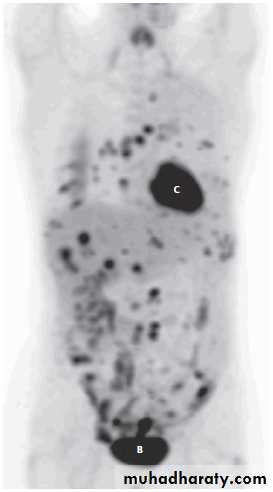

FDG-PET/CT may be used to demonstrate the extent of disseminated disease in order to aid treatment planning .

including FDG-PET/CT, is used in the detection of recurrent disease.